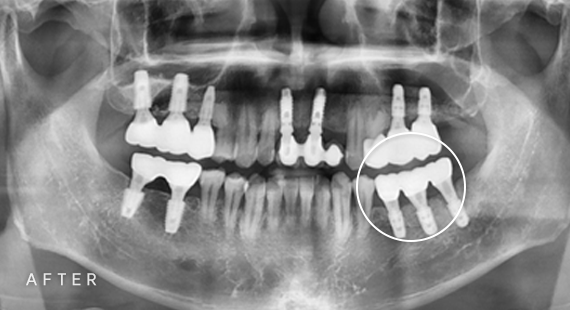

임플란트